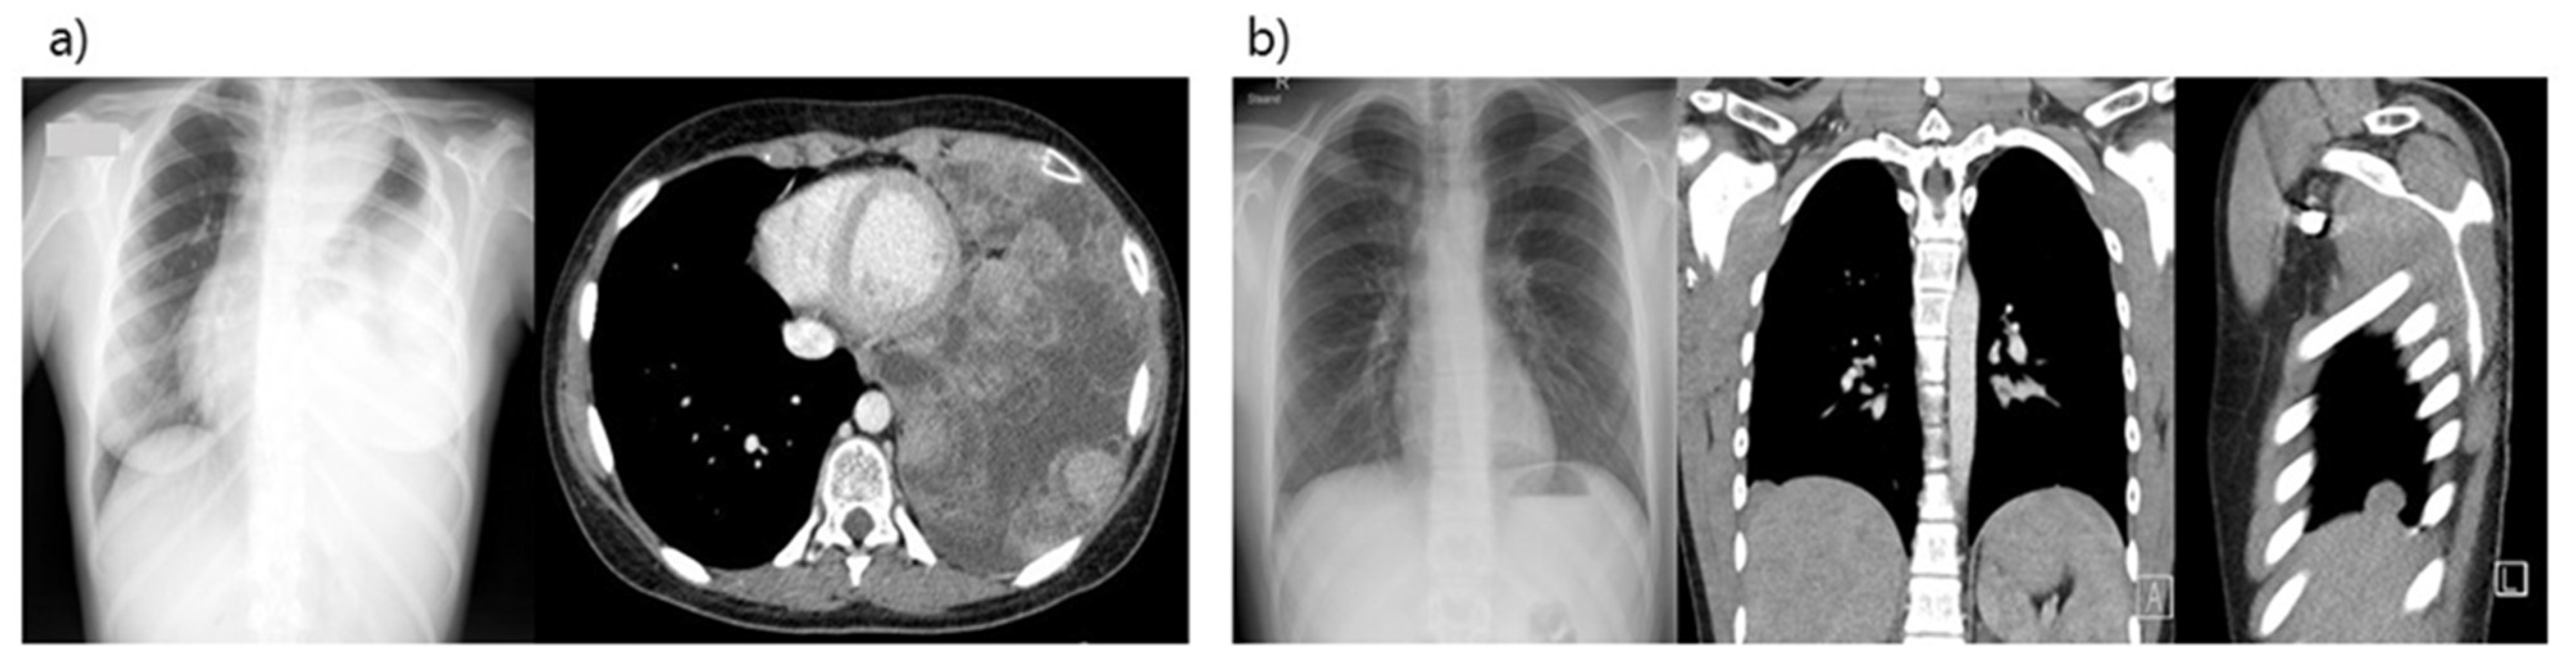

| Pat.nr. | Age at Diagnosis/Sex | Initial Diagnosis | First Line Chemotherapy According Treatment Protocol | Time between End of Treatment and Relapse with Pleuropulmonary Lesions | Number of Relapses | 2nd Line Chemo-Therapy | Histological Response after PP | Additional Therapy after PP | EFS (Months/Years) | OS (Months/Years) | Patient Status (Months/Years after PP) |

|---|---|---|---|---|---|---|---|---|---|---|---|

| 1 | 15 y/Male | Osteosarcoma of the femur | French OS2006 protocol M-EI courses | 28 months | 1 | IE–APx4 | Poor > 10% viable cells | No | 7.1 years | 7.1 years | Alive |

| 2 | 6 y/Male | Osteosarcoma of the humerus | French OS2006 protocol M-EI courses | 11 months | 1 | APx2 | Poor > 50% vital tumor cells. | RT and HD-CT with Thiotepa followed by aSCT | 11.3 years | 11.3 years | Alive |

| 3 | 15 y/Female | Ewing sarcoma of the chest wall | Ewing 99 protocol | Pleural involvement at diagnosis | - | no | Good, rare viable cells.in pleura infiltrated | Hemithoracic RT with boost and VAI x7 | 14 years | 14 years | Alive |

| 4 | 10 y/Female | undifferentiated sarcoma of the chest wall | IA 4x + ICE courses | Pleural involvement at diagnosis | - | AP and palliative vinblastin | Poor > 50% viable cells | Hemithoracic RT | 2 months | 3 months | Died |

| 5 | 10 y/Female | Ewing sarcoma of the pelvis with lung mets | Ewing 99 protocol VIDE courses followed by aSCT (BuMel) | 29 months | 2 all in left lung | TemIri | Poor > 50% viable cells | Hemithoracic RT and Tem + CPT11 vinorelbin + C | 7 months | 10 months | Died |

| 6 | 13 y/Female | Osteosarcoma of the femur | Euramos protocol: MAP courses + IE because of radiological progression | 22 months | 3 | GD | Poor vital tumor cells in pleura parietalis | RT and Ca E courses | 10 months | 13 months | Died |

| 7 | 16 y/Male | Ewing sarcoma of the rib | Ewing 2008 protocol | Pleural involvement at diagnosis, early recurrence with pleural lesions after primary surgery | 1 | TemIri | Good, no vital tumor cells, but vital cells in biopsy of diaphragm | GD + RT | 1.5 months | 5 months | Died |

| 8 | 15 y/Male | Osteosarcoma of the femur | Euramos protocol: MAP courses | 31 months | 1 | IE | Good < 5% vital tumor cells, no infiltration in pleura | no | 1.5 years | 1.5 years | Alive |

| 9 | 15 y/Male | Osteosarcoma of the femur | Euramos protocol: MAP courses | 15 months | 1 | IE | Good, 0% tumor cells, no infiltration in pleura | GD after local recurrence | 7 months | 11 months | Alive, with recurrence of disease |